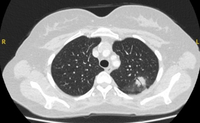

Computed tomography (CT) showing a right upper lobe spiculated solitary nodule within emphysema, in a current smoker with previous asbestos exposure. Note the visible pleural plaque on the left side. Resection histology revealed adenocarcinoma of the lung

From the collection of Dr George Tsaknis, MD, PhD, FRCP(London), MRQA, MAcadMEd, PGCert; used with permission